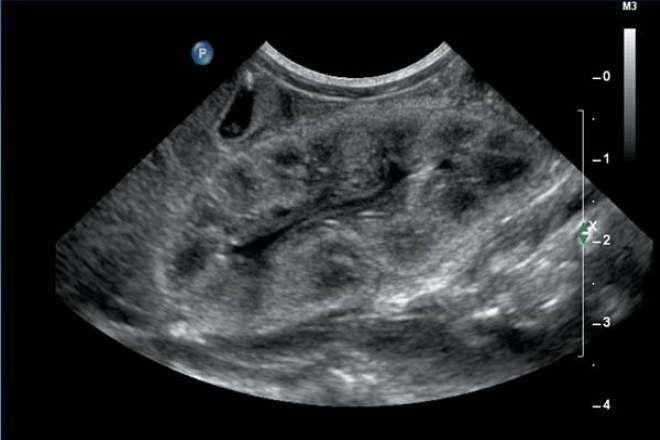

El objetivo del estudio es determinar la frecuencia de masas renales parenquimatosas detectadas de forma incidental mediante el US renal.

El US es una herramienta importante en la evaluación de un tumor cortical renal ya que puede caracterizar una lesión como quística o solida.

Los quistes simples son las lesiones renales benignas más frecuentes representando más del 70% de las masas renales asintomáticas.

Se observa que los quistes simples se encuentran con mayor frecuencia en el sexo masculino, los tumores renales se vieron con más frecuencia en el sexo femenino.